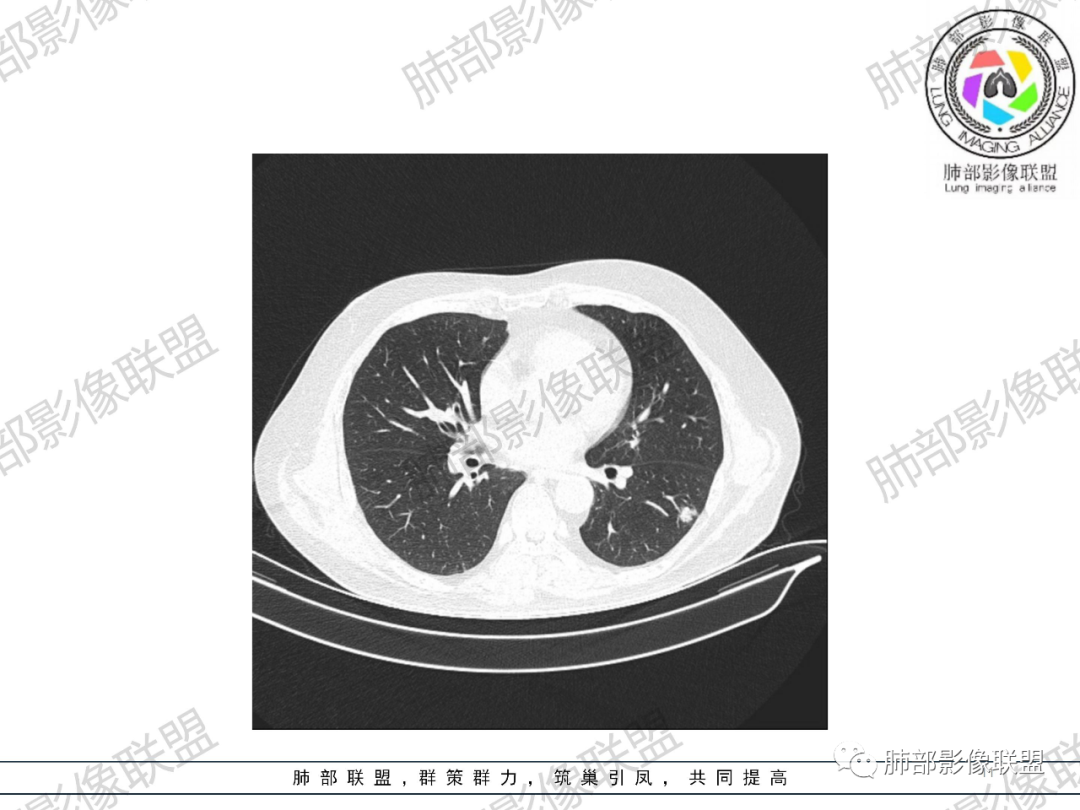

2.19年4月影像显示左肺下叶背段胸膜下浅淡小结节影,边界可分辨,密度不均有堆积感。

19年7月左肺下叶结节影轻度增大,渐至密实,小结节堆积感明显,边缘呈浅分叶。未见支气管进出。

20年8月左肺下叶结节影增大,密度增高,未见钙化及液化空洞。边缘浅分叶并见毛刺,胸膜牵拉线收缩乏力,未形成典型胸膜凹陷。可见供血血管,脐凹征不明显。未见典型卫星病灶。